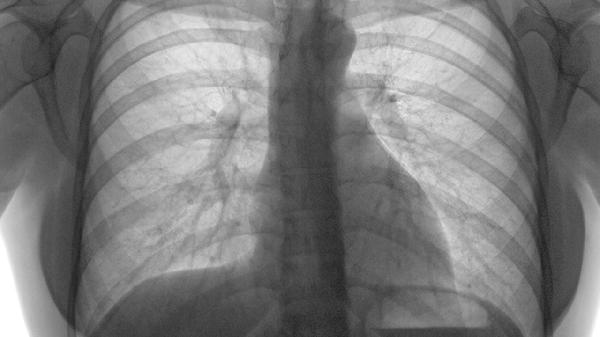

急性肺栓塞主要表现为突发呼吸困难、胸痛和咯血三种凶险症状。急性肺栓塞是由于血栓阻塞肺动脉或其分支导致的急症,可能引发右心衰竭甚至猝死,需立即就医。